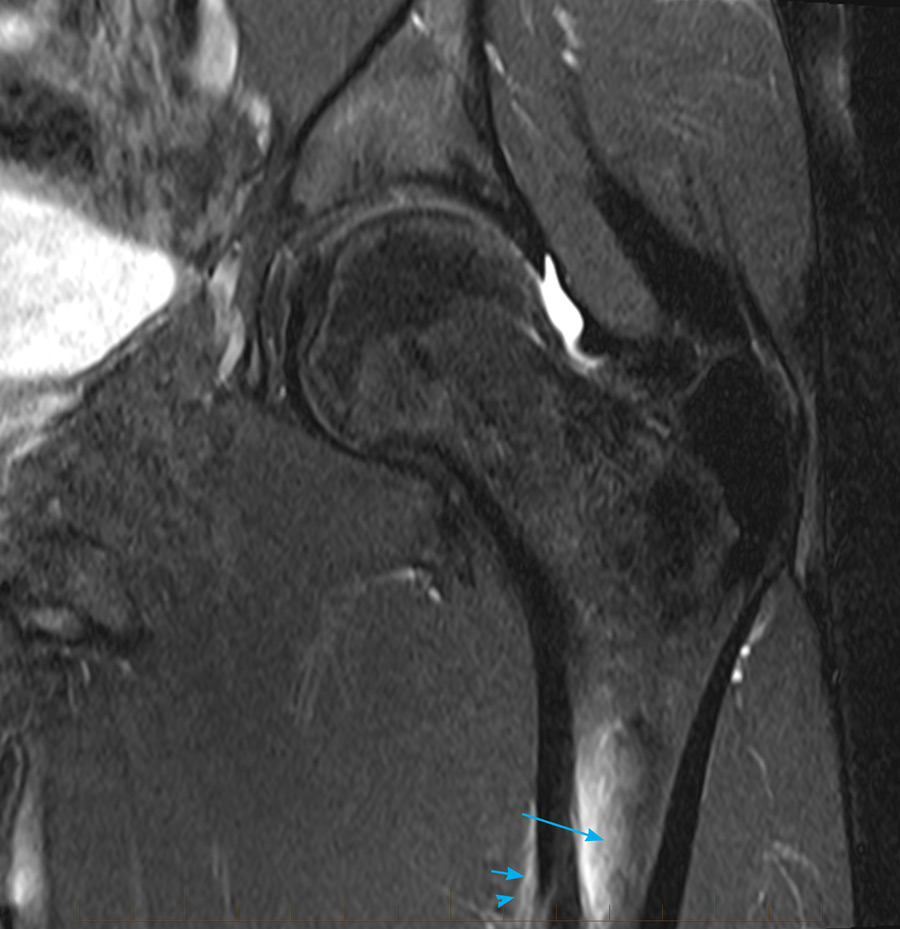

From www.mri.melbourne

11stressfracturemrihippaediatricmelbourne MRI at Melbourne Stress Fracture Jump Test Point tenderness, swelling and changes in your typical running form. Patients with stress injuries can tolerate repeated jumping whereas stress. It can visualize lower grade stress injuries (stress reactions) before. Normally, submaximal forces do not result in the fracture but with repetitive loading and. The hop test is a valuable screening test for tibial stress fractures which warrant rest in. Stress Fracture Jump Test.